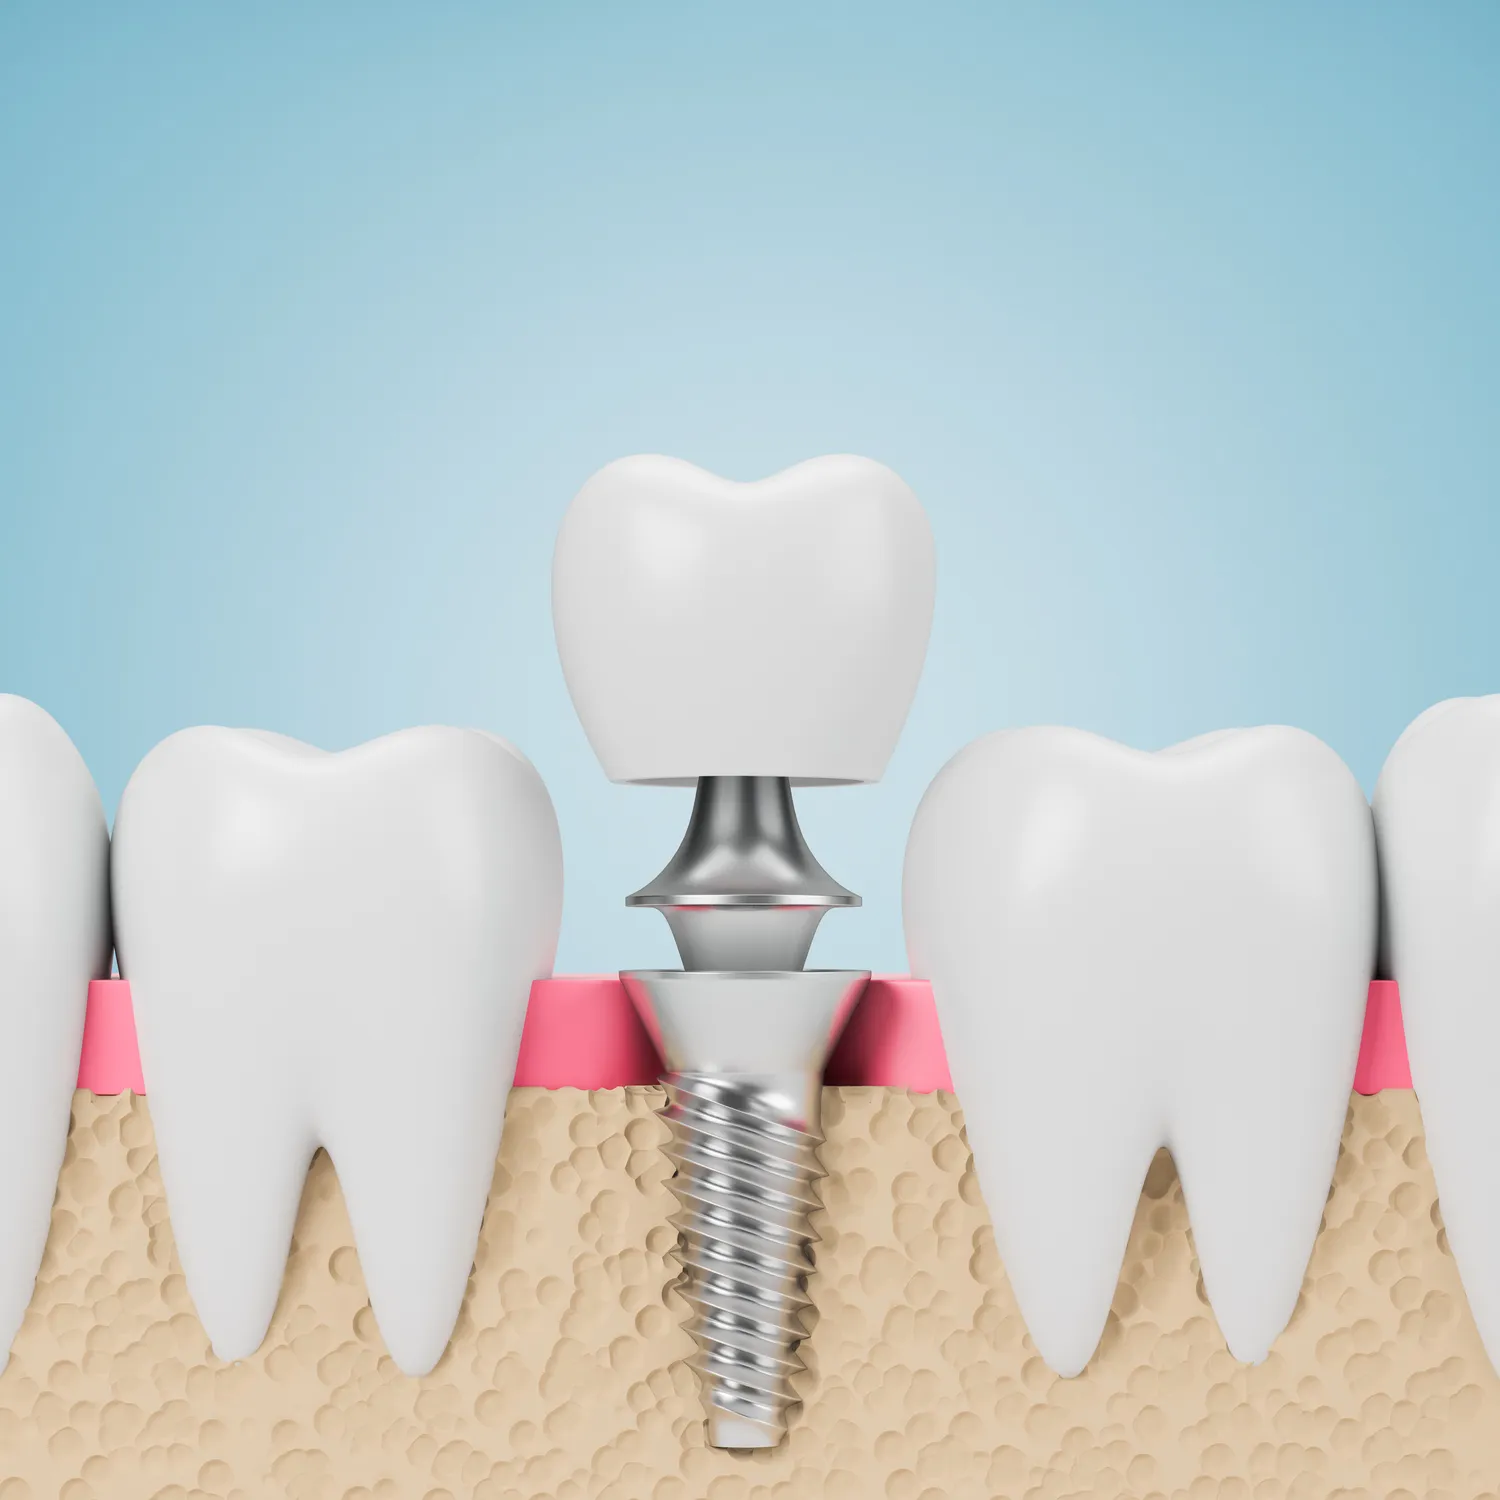

Proces leczenia kanałowego składa się z kilku kluczowych etapów, które mają na celu usunięcie chorej tkanki oraz zabezpieczenie zęba przed dalszymi problemami. Pierwszym krokiem jest dokładna diagnostyka, która obejmuje wywiad lekarski oraz badanie kliniczne. Następnie lekarz wykonuje zdjęcie rentgenowskie, aby ocenić stan korzeni zęba oraz otaczających tkanek. Po postawieniu diagnozy przystępuje do znieczulenia pacjenta, co ma na celu zapewnienie mu maksymalnego komfortu podczas zabiegu. Kolejnym etapem jest otwarcie komory zęba i usunięcie miazgi z kanałów korzeniowych za pomocą specjalistycznych narzędzi. Po oczyszczeniu kanałów lekarz dezynfekuje je i formatuje przed ich wypełnieniem materiałem uszczelniającym. Na koniec lekarz zamyka komorę zęba specjalnym wypełnieniem tymczasowym lub stałym w zależności od stanu zęba oraz planowanego dalszego leczenia.

Nowoczesne technologie mają ogromny wpływ na jakość i efektywność leczenia kanałowego, co znacząco poprawia komfort pacjentów oraz skraca czas trwania zabiegów. Jednym z najważniejszych osiągnięć jest zastosowanie mikroskopów operacyjnych, które pozwalają stomatologom dokładniej ocenić stan korzeni zębów oraz precyzyjniej przeprowadzić zabieg usunięcia miazgi i oczyszczania kanałów korzeniowych. Dzięki mikroskopom możliwe jest zauważenie nawet najmniejszych detali anatomicznych, co zwiększa szanse na skuteczne leczenie i minimalizuje ryzyko powikłań. Innym innowacyjnym rozwiązaniem są systemy endodontyczne wykorzystujące narzędzia rotacyjne wykonane z materiałów superelastycznych; pozwalają one na szybsze i dokładniejsze opracowanie kanałów korzeniowych niż tradycyjne metody ręczne. Dodatkowo nowoczesne materiały uszczelniające stosowane do wypełniania kanałów charakteryzują się wysoką biokompatybilnością i trwałością, co wpływa pozytywnie na długoterminowe wyniki leczenia.